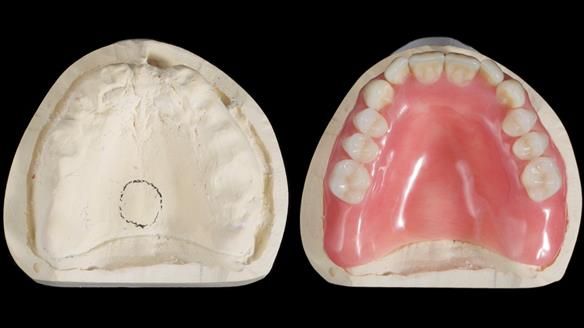

We provided her with an immediate upper denture (Mk 1), followed by a definitive metal-based upper denture (Mk 2). A lower removable partial denture was discussed, to be made only if needed once the upper treatment was complete. However, at review, this wasn’t necessary — Adnana had excellent neuromuscular control and function, even with a shortened dental arch (SDA).

Rowan, Sam Hesketh and Chris Hesketh provided the stunning technical work. I am very lucky to have them.